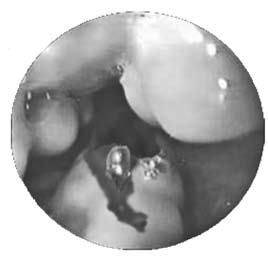

Рис. 83. Эндоскопическая картина при варикозном расширении вен пищевода с признаками кровотечения

Грозным осложнением портальной гипертензии является кровотечение из варикозно расширенных вен пищевода и кардиального отдела желудка. При кровотечении возникает рвота или срыгивание неизмененной кровью, без предшествующих болевых ощущений. При затекании крови в желудок может возникать рвота "кофейной гущей", черный жидкий стул – мелена. У больных появляется бледность, тахикардия, снижение артериального давления. При тяжелой кровопотере возникает геморрагический шок, нередко заканчивающийся летальным исходом. Кровотечение может привести к прогрессированию печеночной недостаточности, даже если до этого была ее компенсация. Оно осложняет цирроз печени почти в половине случаев, летальность при этом достигает 60 % (рис. 83).